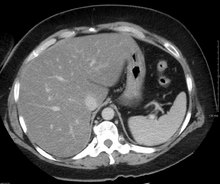

Liver steatosis (fatty liver disease) as seen on CT

Imaging studies are often obtained during the evaluation process. Ultrasonography reveals a "bright" liver with increased echogenicity. Medical imaging can aid in diagnosis of fatty liver; fatty livers have lower density than spleens on computed tomography (CT), and fat appears bright in T1-weighted magnetic resonance images (MRIs). No medical imagery, however, is able to distinguish simple steatosis from advanced NASH. Histological diagnosis by liver biopsy is sought when assessment of severity is indicated.